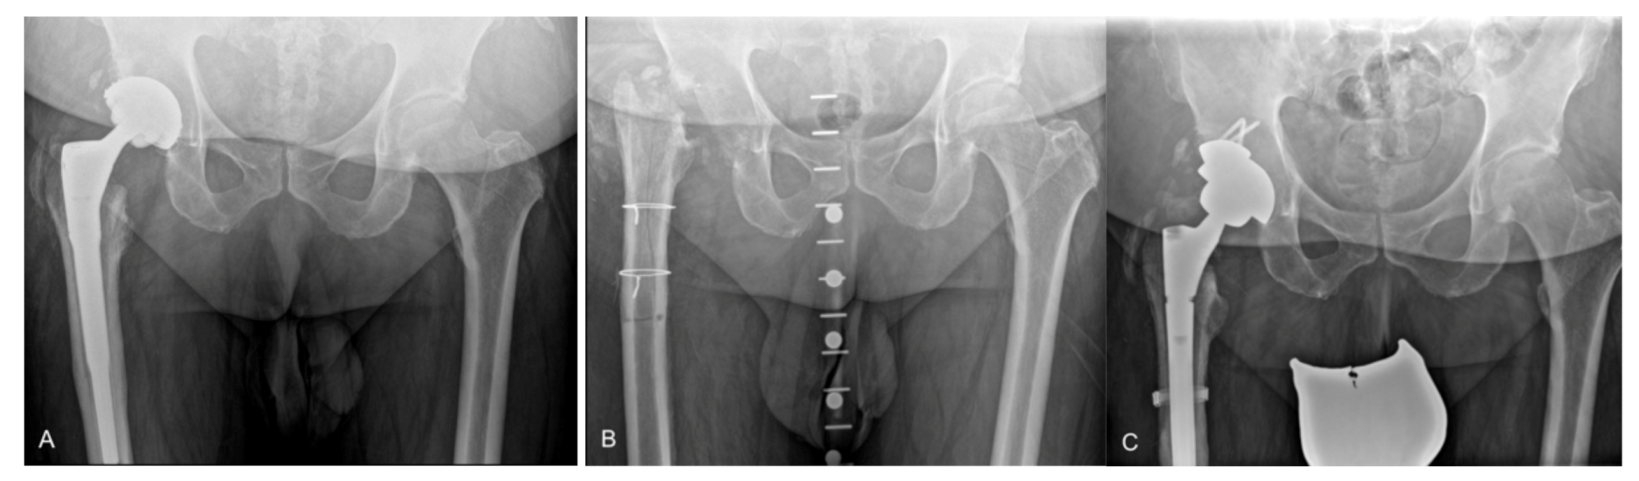

| Radiographic results | |||

| ETO fragment fracture | 4 (13%) | 5 (8%) * | 0.458 |

| ETO migration (>5 mm) | 1 (3%) | - | |

| Union of ETO | 31 (97%) | - | |

| Femoral stem subsidence (>5 mm) | 4 (13%) | 6 (9%) | 0.637 |